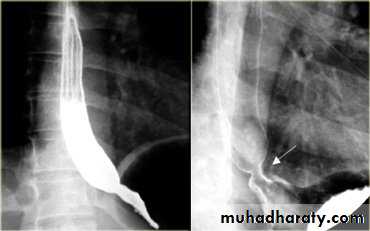

• 2- Arise from anterior wall and extend Posteriorly .• 3- Lateral view Ba. Swallow show self like filling defect with proximal dilatation.

• 4-Single or multiple.

ESOPHAGEAL WEB

10% incidence at autopsy

Can be congenital or acquiredMost in hypopharynx and proximal esophagus

Majority protrude from anterior esophageal wall

Symptoms if lumen > 50% compromised

Sideropenic dysphagia (Plummer-Vinson syndrome)

Iron deficiency anemia

Esophageal web with dysphagia

Increased incidence of carcinoma

Validity of syndrome debatable